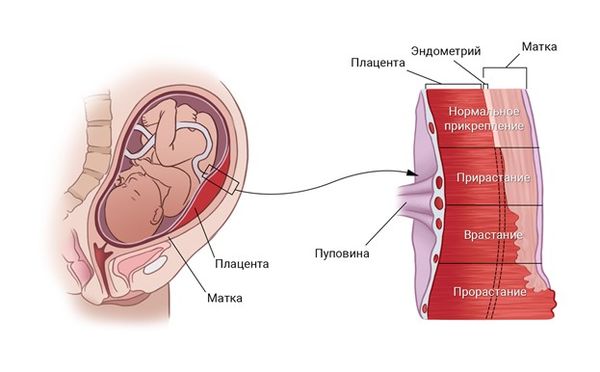

Околоплодный пузырь и плацента: структура и функции